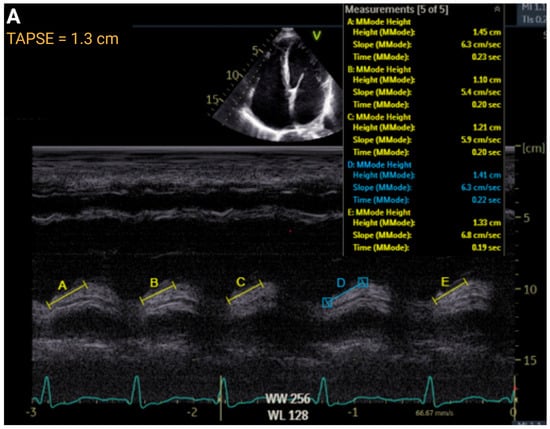

| TAPSE, cm | >1.7 | ≤1.7 to ≥1.3 | ≤1.3 to >1.0 | ≤1.0 | r = 0.45 to 0.62 | AUC = 0.74 |